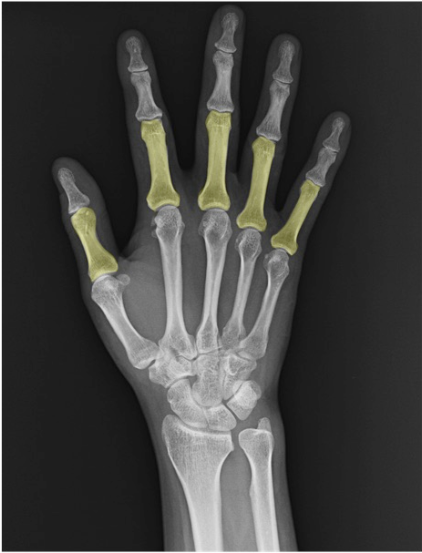

関節

CM関節(carpometacarpal joint / CMC joint)

遠位手根骨と中手骨基部の関節。第1CMC(母指)は鞍関節(saddle)で可動性大。他のCMCは平面関節が主体で、PA像では関節裂隙の均等性を確認します。

IP関節(interphalangeal joint)

指節骨間の関節。母指はIPのみで、他指のPIP/DIPに相当。正面像で裂隙幅と骨棘・骨硬化の有無に注目。

MP関節(metacarpophalangeal joint / MCP)

中手骨頭と基節骨底の関節。PA像で楕円形の関節裂隙と均等性、側面像で背側板(示唆)や脱臼の有無を評価。

PIP関節(proximal interphalangeal joint)

第2~5指の近位指節間。PA像で裂隙均等性、側面像で関節面平行性を確認。変形性変化や外傷性変化のファーストチェックポイント。

DIP関節(distal interphalangeal joint)

第2~5指の遠位指節間。末節骨基部の骨硬化・骨棘や石灰化沈着などを確認。